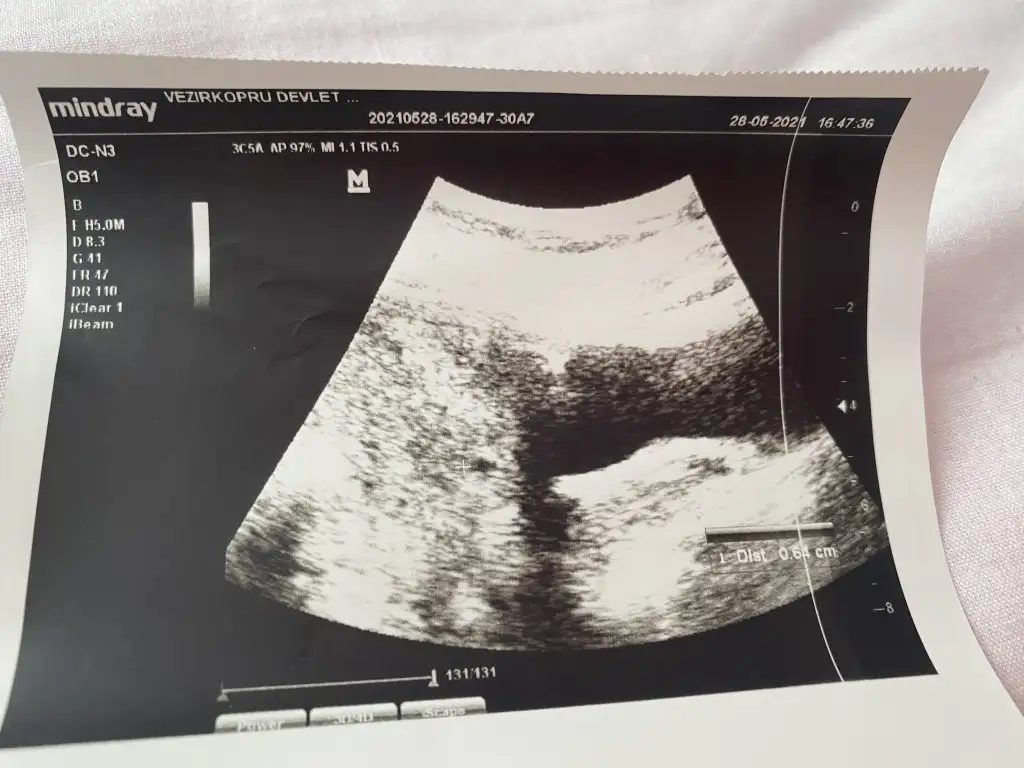

Merhaba ben 15 Nisanda kürtaj oldum.Adet olmadan kürtajdan 40 gün sonra hamile olduğumu öğrendim 25 Mayısta kese karından görünmedi alttan bakınca doktor yeni oluşan bi kese olduğunu düşündü 28 mayısta karından keseyi gördü.Keseye göre 5 hafta dedi.(5 hafta olma imkanı yoktu ama adet tarihine göre hesaplamadan dolayı 2 hafta fazla gibi hesaplandığından galiba ) 2 hafta sonra gel kalbine bakalım dedi.İlk hamileliğimde 6+2 de bebeğin kalbi durmuştu bende dayanamadım 11 gün sonra (8 Haziranda) 6+4 olması gereken zamanda özele gittim. Doktor henüz kesenin küçük olduğunu 20 mm olduğunda kalp atışının duyulduğunu söyledi.Keseye göre 6+3 tü bir güne takılmadım cihazdan da farkedebilir.Bebek çok küçük bir nokta şeklindeydi tutunmuş dedi. 2-3 hafta sonra gel dedi kalp için. 1 hafta geçtikten sonra ben devlete gittim. Kendi göründüğüm doktorun işi çıkmış gitmiş. Başka bir doktora göründüm ama o doktora hiç güvenmiyorum baktı daha kalp atışı yok 2 hafta sonra gel dedi kaç haftalık göründüğünü sordum 5+6 dedi (normalde 7. Haftada olması lazım) durumu anlattım bir hafta öncesinde 6+3 dendiğini doktor benim cihazımda ben bu şekilde ölçtüm 2 hafta sonra gel demekten başka bir şey söylemedi. Tabi haftasını o şekilde söyleyince ben kafamda bitirdim yine kalbi durdu diye düşündüm.O günden sonra kahverengi lekelenme başladı akıntının içinde kan görünce ben bebeği düşüreceğimi düşündüm korktum. Devletteki diğer doktor gelmişti ona gittim durumu anlattım baktı kese düzgün görünüyor dedi. Özelde çok küçük bi noktada olan bebek daha belirgin görünüyordu bu sefer Keseye göre değil de bebeğe göre ölçtü 6+1 çıktı 2 gün önceki ile de uyumluydu ama önceki haftalarla uyumlu değil. Kalp atışı yine yoktu.Kendimce düşünüyorum diğerlerinde Keseye göre ölçülmüştü şimdi bebeğe göre ölçüldüğü için mi acaba diyorum ama kese 8 haziranda da 17 haziranda da 13 mm idi. Kese gelişmeden bebek gelişir mi anlamadım. Doktor progestan verdi 1 hafta sonra gel dedi dinlenmemi bol su içmemi ilişkiye girmememi söyledi. Progestanı kullanıyorum ama acaba ölü bebeği mi karnımda tutuyorum ilaç kullanarak diye düşünüyorum.Güvenmediğim doktor hariç ultrason görüntülerini vermişti aşağıya ekledim birisi hariç diğerleri devlet. Bu konuda bilgisi olan benzer durum yaşayan yardımcı olur musunuzBen zaten kötüyü kabullendim gerçek neyse onu öğrenmek istiyorum